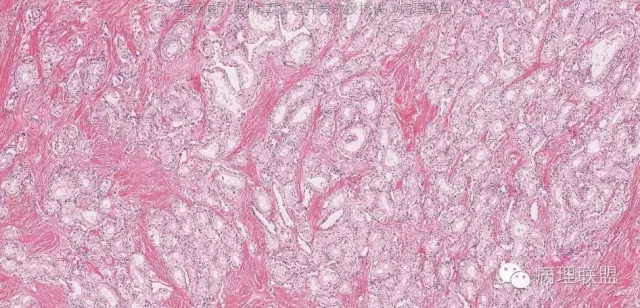

肿物与正常胰腺组织分界清楚,肿瘤组织被纤维组织分隔成巢状。

肿瘤细胞排列成腺管状或腺泡状,腺管或腺泡排列紧密,背靠背。瘤细胞形态与浆液性囊腺瘤的瘤细胞形态完全一致。因此,诊断为浆液性囊腺瘤,实体型。